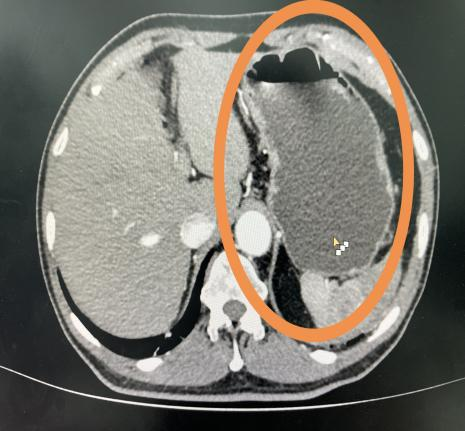

饮水前                                   饮水后